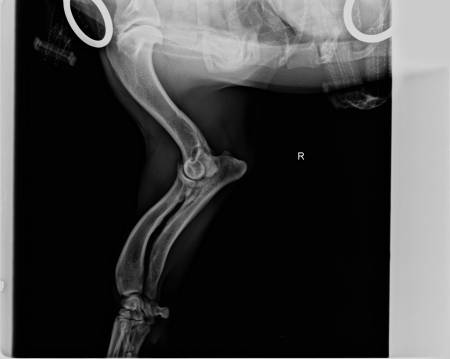

wie einige von euch ja wissen, war ich heut mit Sammy bei Dr. Thiet in Isernhagen in der Kleintierklinik um Sammy seine Krummbeine zu röntgen. Ich hatte ja Angst, dass die Beine sich noch weiter nach aussen drehen könnten, was zum Glück nicht bestätigt wurde. Soviel dazu.Hier erstmal die Röntgenbilder:

Der Arzt hat gesagt dass Elle und Speiche glücklicherweise im richtigen Winkel nebeneinander liegen aber dass er eine Entzündung am Gelenk entdeckt hat.

Um die Herkunft der Entzündung genauer zu bestimmen, müsste mit Sammy ein CT gemacht werden. Er würde sonst aufschneiden müssen um genauer zu schauen, aber er würde gern erst genau wissen (durch das CT) was diese Entzündung auslöst.Komischerweise hat er mir gegen diese Entzündung nichts gegeben (fällt mir jetzt erst auf wo ich zu Hause bin) und mir bloß gesagt, dass ich mir das mit dem CT noch überlegen kann (300,-€ !!!) da es jetzt nicht unbedingt so akut sei und Sammy ja keine Schmerzen hat. Ausserdem soll ich die Stellung seiner Pfoten beobachten und ihn keine Treppe mehr herunterlaufen lassen. Daran halte ich mich jetzt auch.